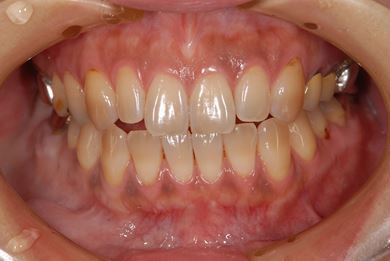

治療後

• 治療後